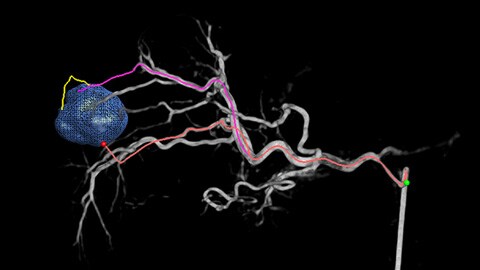

La solución de Detección automática de alimentadores puede mejorar, de forma significativa, la detección de arterias nutricias. EmboGuide le ayuda a maximizar la eficacia de sus procedimientos de quimioembolización transarterial (QET), ya que potencialmente mejora su sensibilidad, reduce los falsos positivos y maximiza la concordancia entre lectores1. EmboGuide también proporciona una guía 3D, en vivo, eficiente y basada en el flujo de trabajo con detección automática de alimentadores1.

La adopción de técnicas de quimio/radioembolización como la QET y la Radioterapia interna selectiva (Selective Internal Radiotherapy, SIRT) impulsa la necesidad de estandarización y eficiencia. Caso tras caso, debe localizar de manera confiable y uniforme los tumores, identificar todos los vasos nutricios y planificar/llevar a cabo el enfoque intervencionista apropiado. Nuestra solución de Detección automática de alimentadores puede mejorar, de manera significativa, la detección de arterias nutricias en comparación con la TC de haz cónico sola. EmboGuide le ayuda a maximizar la eficacia de sus procedimientos de QET, ya que potencialmente mejora su sensibilidad, reduce los falsos positivos y maximiza la concordancia entre lectores.1

La capacidad de detectar y de distinguir nódulos hepáticos e identificar los vasos minúsculos del alimentador es fundamental para determinar el tratamiento apropiado. Navegar a la región de interés y llegar a todos los alimentadores, sin dejar de ser selectivo con la lesión, aumenta la oportunidad de éxito. La confirmación del punto final del tratamiento y el éxito de este mientras el paciente está todavía en la mesa incrementa la confianza en los resultados clínicos.